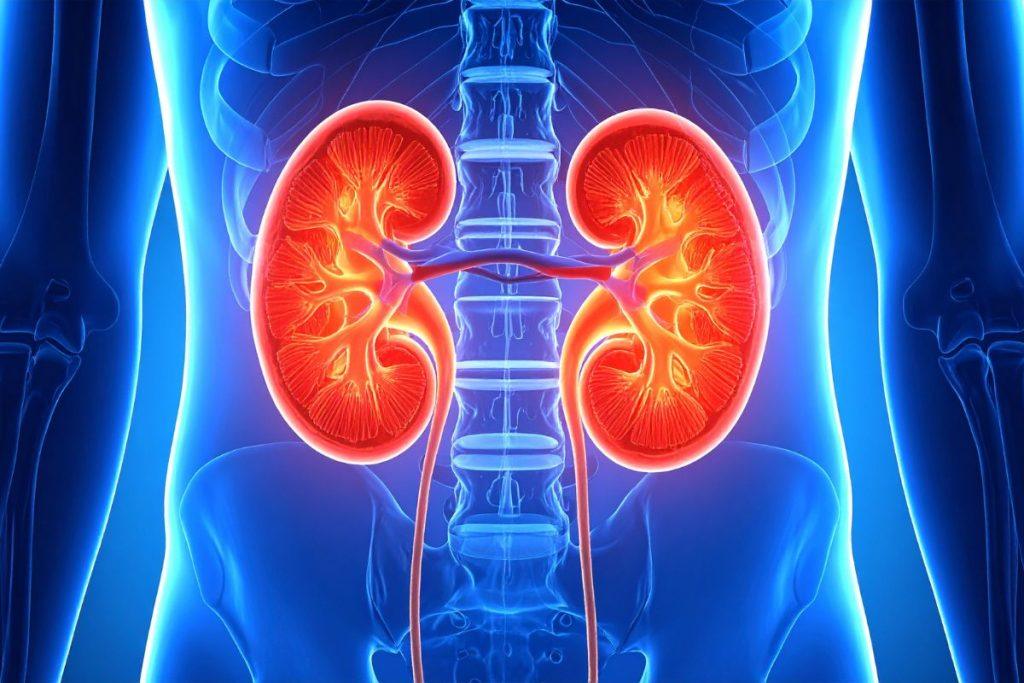

Inkstų sveikata

Kiekvieną dieną jūsų inkstai išvalo apie 115–140 litrų kraujo, iš viso susidaro 1-2 litrai šlapimo, kurį sudaro atliekos ir skysčių perteklius. Kartu su kepenimis, inkstai yra pažangiausia valymo sistema gamtoje.

Aktyvuota anglis padeda pašalinti šlapalą ir kitus šlapimo toksinus, mažina inkstų apkrovą ir skatina sveiką filtraciją. Tai ypač svarbu žmonėms, kurie dažnai vartoja perdirbtą maistą ar turi polinkį į inkstų akmenligę. Reguliarus anglies vartojimas gali sumažinti uždegimų tikimybę ir palaikyti ilgalaikę inkstų funkciją.